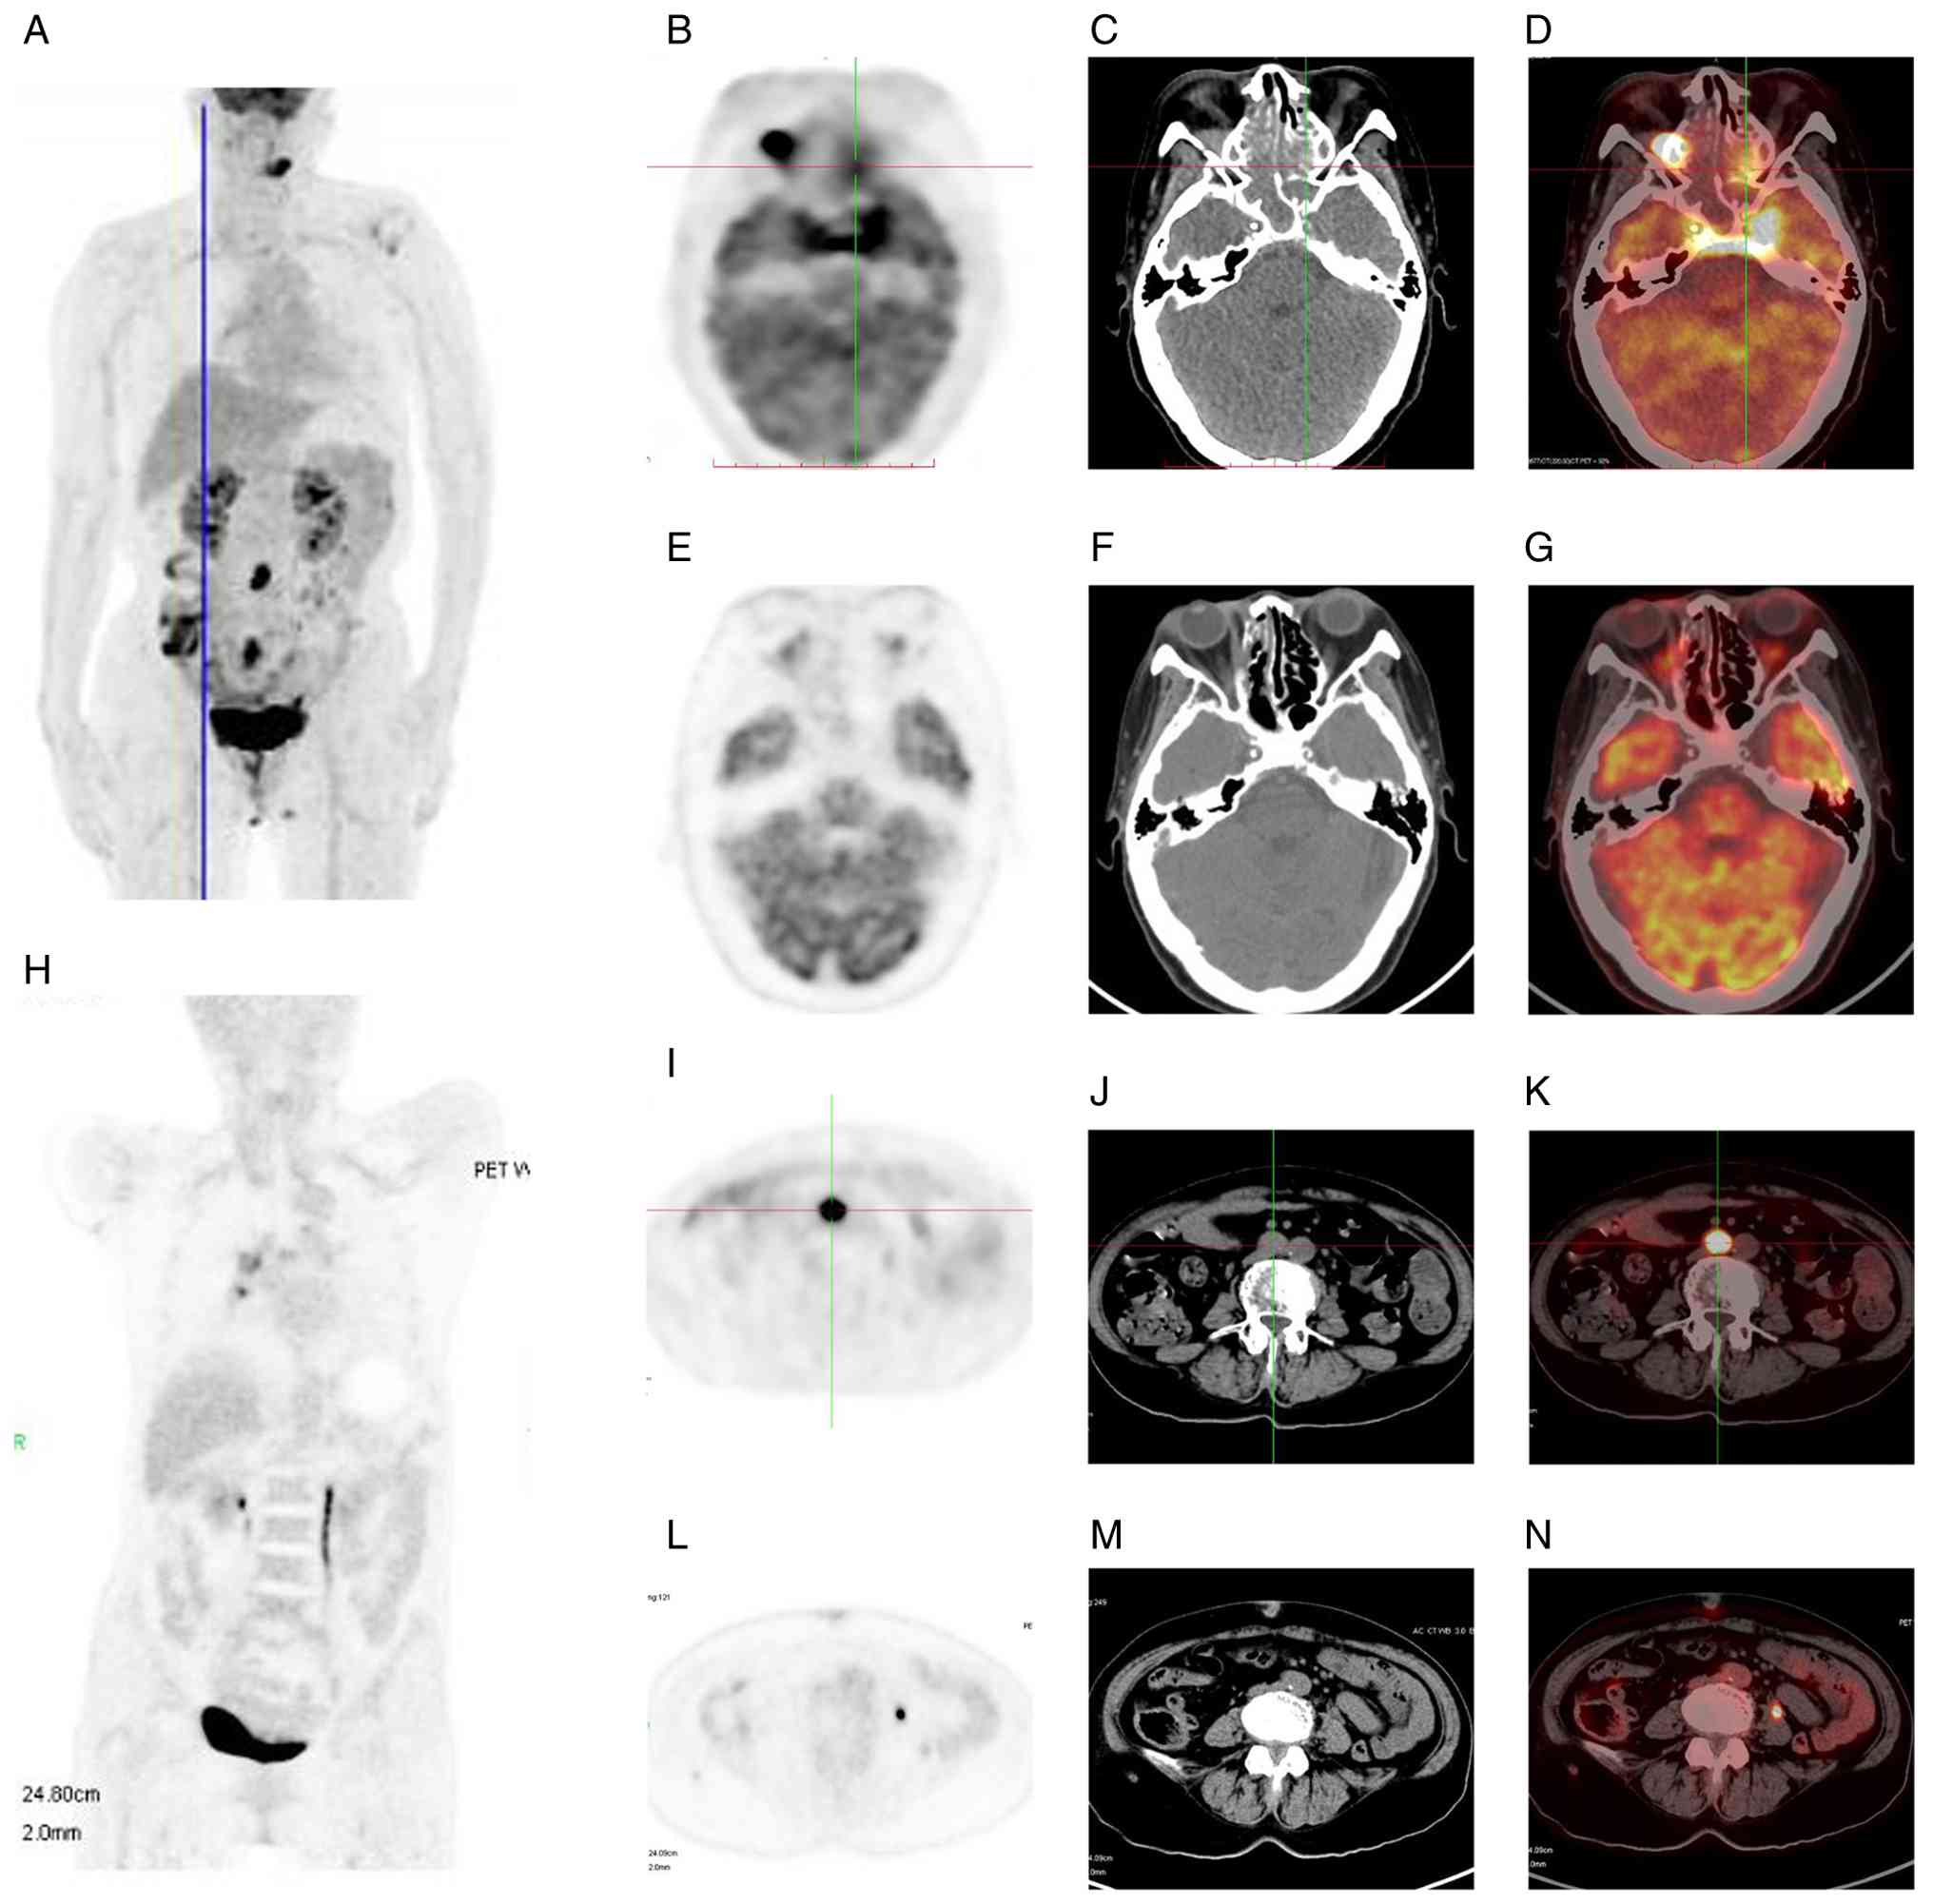

Positron emission tomography-computed tomography (PET-CT) subsequently revealed multiple lesions with abnormally increased fluorodeoxyglucose (FDG) uptake, involving the ethmoid sinus, sphenoid sinus, bilateral CSs, right orbital mass, periaortic and pelvic lymph nodes, sacral spinal canal and left mandibular medullary cavity (Fig. 3A, C-E and I-K). The right orbital apex and periaortic lymphadenopathy showed the highest FDG uptake, with the maximum standardized uptake value (SUVmax) of 11.72 and 12.77, respectively. SUVmax values for the sphenoid sinus, bilateral CSs, sacral spinal canal and left mandibular medullary cavity were 6.31, 9.37, 8.69 and 8.57, respectively.

18F-FDG PET/CT images of

the patient with intravascular large B-cell lymphoma. (A) Maximum

intensity projection images at baseline. (B) Baseline PET image of

the CS, orbit and sinuses. (C) Baseline CT scan image corresponding

to image B. (D) Baseline PET/CT fusion image of the CS, orbit and

sinuses demonstrating intense FDG uptake in the bilateral CSs and

right orbital mass. (E) Follow-up PET image after treatment

corresponding to image B. (F) Follow-up CT image after treatment

corresponding to image C. (G) Follow-up PET/CT fusion image after

treatment corresponding to image D showing complete metabolic

resolution of the right orbital lesion and absence of abnormal FDG

uptake in the orbit or CSs. (H) Maximum intensity projection images

after eight cycles of R-CHOP regimen. (I) Baseline PET image of the

abdomen. (J) Baseline CT scan image of the abdomen. (K) Baseline

PET/CT fusion image of the abdomen revealing marked FDG uptake in

the lymph nodes surrounding the abdominal aorta. (L) Follow-up PET

image after treatment corresponding to image I. (M) Follow-up CT

image after treatment corresponding to image J. (N) Follow-up

PET/CT fusion image after treatment corresponding to image D

demonstrating no enlarged lymph nodes or high radiotracer uptake in

the abdominal cavity. (B-N) Axial view. CS, cavernous sinus;

PET-CT, positron emission tomography-computed tomography; FDG,

fluorodeoxyglucose; R-CHOP, rituximab, cyclophosphamide,

doxorubicin, vincristine and prednisolone.

Figure 3.

18F-FDG PET/CT images of the patient with intravascular large B-cell lymphoma. (A) Maximum intensity projection images at baseline. (B) Baseline PET image of the CS, orbit and sinuses. (C) Baseline CT scan image corresponding to image B. (D) Baseline PET/CT fusion image of the CS, orbit and sinuses demonstrating intense FDG uptake in the bilateral CSs and right orbital mass. (E) Follow-up PET image after treatment corresponding to image B. (F) Follow-up CT image after treatment corresponding to image C. (G) Follow-up PET/CT fusion image after treatment corresponding to image D showing complete metabolic resolution of the right orbital lesion and absence of abnormal FDG uptake in the orbit or CSs. (H) Maximum intensity projection images after eight cycles of R-CHOP regimen. (I) Baseline PET image of the abdomen. (J) Baseline CT scan image of the abdomen. (K) Baseline PET/CT fusion image of the abdomen revealing marked FDG uptake in the lymph nodes surrounding the abdominal aorta. (L) Follow-up PET image after treatment corresponding to image I. (M) Follow-up CT image after treatment corresponding to image J. (N) Follow-up PET/CT fusion image after treatment corresponding to image D demonstrating no enlarged lymph nodes or high radiotracer uptake in the abdominal cavity. (B-N) Axial view. CS, cavernous sinus; PET-CT, positron emission tomography-computed tomography; FDG, fluorodeoxyglucose; R-CHOP, rituximab, cyclophosphamide, doxorubicin, vincristine and prednisolone.

Following four initial cycles of rituximab, cyclophosphamide, doxorubicin, vincristine and prednisolone (R-CHOP) (600 mg rituximab on day 0, 1 g cyclophosphamide on day 1, 100 mg doxorubicin on day 1, 4 mg vincristine on day 1, 100 mg/day prednisolone on days 0–5) combined with the Bruton tyrosine kinase (BTK) inhibitor (320 mg/day Zanubrutinib), the frontal numbness and pain of the patient was improved. However, MRI revealed an enlarged CS lesion (Fig. 1I and J), and the patient agreed to undergo high-dose methotrexate (HD-MTX) therapy (3.5 g/m2 intravenously). After six cycles of R-CHOP combined with BTKi and two courses of HD-MTX, MRI showed a marked reduction in the CS lesion (Fig. 1K and L); however, complete remission had not yet been achieved. To further pursue complete remission, the patient agreed to receive an additional two cycles of R-CHOP. Therefore, two cycles of the same regimen (600 mg rituximab on day 0, 1 g cyclophosphamide on day 1, 100 mg doxorubicin on day 1, 4 mg vincristine on day 1, 100 mg/day prednisolone on days 0–5 and 320 mg/day Zanubrutinib, each cycle lasting 21 days) and two courses of HD-MTX (3.5 g/m2 intravenously) were administered. Following treatment, the diplopia, frontal numbness, bilateral ptosis and ophthalmoplegia resolved completely. Post-treatment MRI and PET-CT demonstrated marked reduction of CS enhancement and orbital mass resolution (Figs. 1M-O and 3B, F-H and L-N). Zanubrutinib (320 mg/day) was administered as maintenance therapy after chemotherapy. However, diplopia recurred again 3 months later. The patient received volumetric-modulated arc radiotherapy at 36 Gy in 18 fractions to the elective clinical target volume, including the bilateral orbits, bilateral nasal cavities, sphenoid sinus, bilateral CSs and sellar region. After completing radiotherapy, the patient declined further in-person follow-up visits. However, a recent telephone follow-up was successfully conducted at 1 year post-treatment, at which time the patient reported being alive, without ptosis and with nearly normal ocular motility.